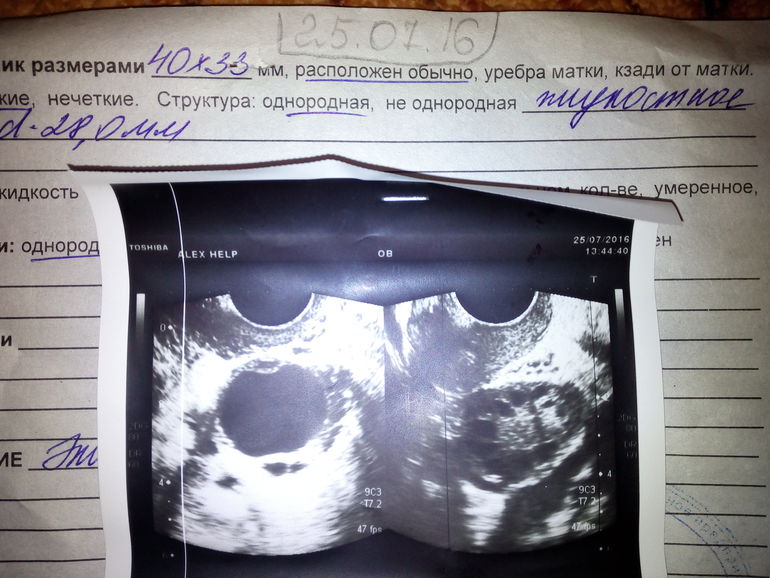

КОНСУЛЬТАЦИИ ВРАЧЕЙИ снова здравствуйте! Я к вам со следующей проблемой .Была на УЗИ .и вот что произошло на последнем.Врач в отпуске.Можно ли подождать с таким результатом последнего УЗИ или срочно к любому доктору?Как же с этим быть?

Фолликулярная киста это не страшно, она образуется из фолликула, который не овулировал в этом цикле. Это не редкое явление. Обычно при диагностировании фолликулярной кисты, лечение ограничивается регулярным наблюдением и выжидательной тактикой в течение 2-3 циклов, при этом в динамике следует прослеживать изменение размеров кисты с помощью УЗИ. Чаще всего, она рассасывается сама. Просто будьте чуть бережнее к себе в последующий цикл. А вот гидросальпинкс - вещь серьезная, но редко обнаруживаемая по УЗИ (стоит перепроверить этот диагноз). Вы на какой день цикла делали УЗИ и зачем делаете так часто вообще?

Отчасти оба правы и неправы. УЗИ - очень условный метод диагностики, все зависит от того, кто смотрит. Гидросальпинкс на УЗИ практически невозможно рассмотреть, а если лапароскопия у вас уже была в недавнем времени - его бы увидели. Косвенные признаки аденомиоза врач ставит, скорее всего, из-за того, что видит неоднородную структуру и нечеткий контур, но это вполне может быть просто из-за того, что врач так видит (точно можно сказать на гистероскопии, но не по УЗИ). А фолликулярную кисту врач и на втором узи видит, только называет ее "округлое жидкостное образование типа фолликула". И снова очень маленький эндометрий (всего 4 мм). Вам нужно искать грамотного врача: это очень разные диагнозы и без должного обследования они не ставятся. Тем более, без должных оснований не назначаются КОК.